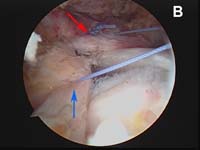

For the most common type of rotator cuff tears, the tendon of the rotator cuff muscle called the supraspinatus will have torn and pulled back slightly from its normal attachment at the greater tuberosity atop the humerus. These smaller tears which are "non-retracted" or "minimally-retracted" only need to be freshened or débrided back to stable, healthy tendon tissue, then mobilized back to the tuberosity and fixed in place. (See Fig. 9) When using an all arthroscopic technique, the surgeon will employ special devices called "suture anchors" to hold the tear in position when it heals. These "anchors" can be made of metal or absorbable compounds. They are screwed or pressed into the bone of the attachment site and the attached sutures are used to tie the edge of the rotator cuff in place.

As tears become larger, they deform and the tendon tissue "shrinks". Thus, larger tears need to be refashioned, repaired side-to-side, or "zipped" closed using a technique called margin convergence. This technique is analogous to zippering shut an open tent flap. The rotator cuff tissue is freed from a scarred, retracted position and repaired side-to-side to ‘close the tent flap’ and restore the tissue over the top of the humeral head. (See Fig.4 and Fig.10) The repaired cuff tissue is then fixed to the site it originally tore away from using specially-designed implants called suture anchors. These are metallic or absorbable plastic devices that secure sutures to the bony attachment. The sutures are then sewn through the torn edge of the cuff to complete the repair.